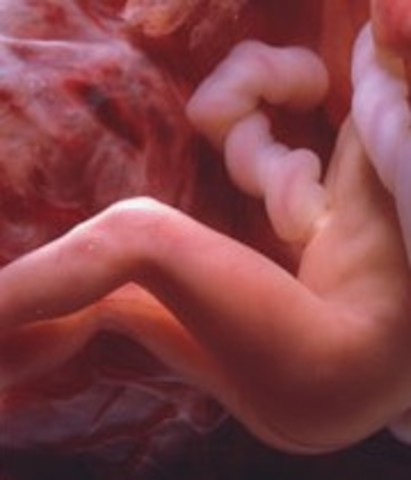

• Week 6: The Heart Begins to Beat

Week 6: The Heart Begins to Beat

Spinal cord is closing, brain is splitting into five parts, a tiny little heart forms and will begin to beat, and the arms and legs are begiining to go into place from their cells. Oxygen and nourishment will be given to the baby through its developing umbilical cord.

• Week 7: Arms and legs Begin to Grow

Week 7: Arms and legs Begin to Grow

The heart has one chamber and is now beating. The arms and legs are beginning to bud. The lungs, the liver, the pancreas and the thyroid gland are beginning to form.